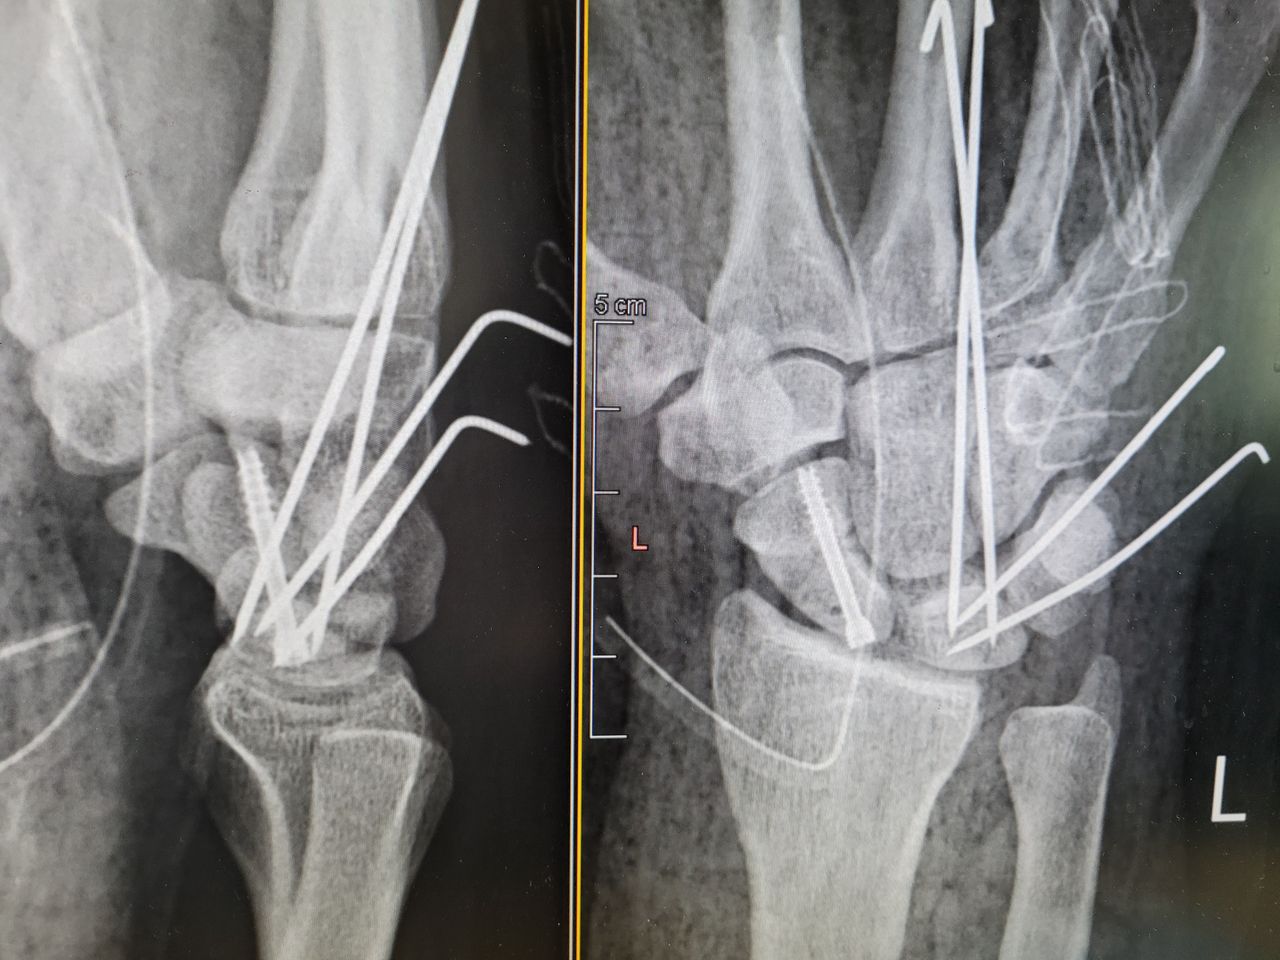

Rekonstrukcje stawów rzekomych kości łódeczkowatej z przeszczepami kostnymi.

Złamania kości. Skręcenia i zwichnięcia stawów.

Zdjęcia i filmy

Ortopeda Mateusz Orzechowski to świetny lekarz ,bardzo profesjonalny. Po nie udanej operacji innego lekarza ,odbijając się od roznych gabinetów, jako jedyny wykazał chęć pomocy. Po wypadku że szkłem w dłoni ,zerwane zostały sciegna ,mięśnie i nerwy .Doktor wykonał skomplikowana operacje rekonstrukcji zginaczy ,dzięki której po mału wracam do sprawności juz po 3 miesiacach.Nadal pozostajac zaopiekowaną do zakonczenia leczenia.Wszystkie wizyty odbywają się na czas. Proces leczenia jest szczegółowo omawiany na wizycie,jak również przed planowana operacja. Serdecznie polecam i dziękuję;)